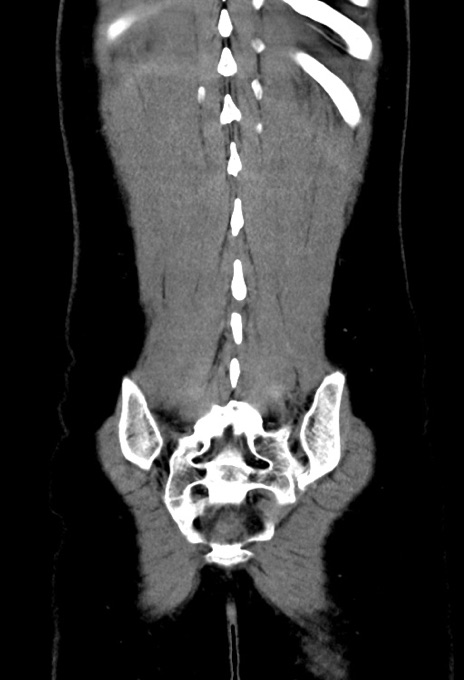

症例17(冠状断像)

【症例】20歳代女性

【主訴】嘔吐、下腹部痛

【現病歴】昨日夕食後に嘔吐し下腹部痛が出現。本日になっても嘔吐持続し改善しないため来院。

【身体所見】意識清明、BT 37.2℃、BP 108/67mmHg、腹部:平坦、やや硬、下腹部正中から右にかけて圧痛あり、反跳痛軽度あり、tapping pain(+)。

【データ】WBC 13600、CRP 14.94